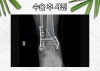

상담을 요청하신 의뢰인은 한 스포츠 센터의 설비를 봐주시며 일하시고 계셨습니다. **2M 높이에서 **일하시던 중 그만.. 떨어지는 사고를 당하는 추락사고를 겪으셨습니다. 발목이 부어오르며 통증을 호소하셨고 인근 병원으로 긴급하게 후송되셨죠.

병원에 내원하여 정밀 검사를 받은 결과, 우측 삼복사 골절.

쉽게 말하자면 오른쪽 발목의 3개의 면이 모두 골절된 것을 의미합니다.

삼과 (삼복사) 골절 진단받아 수술적 치료를 시행해야 했고, 플레이트와 핀을 고정하는 금속 고정술을 받으셨습니다.